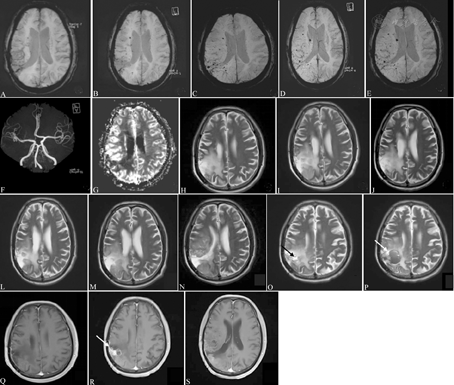

病例2:男性,反复住院4年,初次住院时66岁,因"左上肢无力2 d"于2013年10月18日入院。患者于入院前2 d活动时出现左手无力,持物不稳,伴头晕、视物模糊、左侧口角流涎,恶心、呕吐1次,呕吐物少,未在意。因症状持续无缓解来院门诊,并收入神经内科。既往史:11年前因"脑胶质瘤(右顶叶)"行手术切除,术后5个月给予放射治疗33次,总剂量60 Gy,未化疗。1年前出现左侧肢体抽搐,上肢屈曲,下肢伸直,持续2 min,发作10余次,诊断为"继发性癫痫",给予丙戊酸钠和托吡酯治疗,未再出现肢体抽搐。有高血压史20年,血压最高180/103 mmHg,规律口服"氨氯地平、厄贝沙坦",血压控制于140/80 mmHg左右。2型糖尿病史16年,饮食控制,未用药,空腹血糖6~8 mmol/L。入院查体:神志清楚,智能正常,言语清晰,双侧额纹、鼻唇沟对称,左上肢肌力5-级,感觉、共济正常,双侧病理征阴性。入院诊断:(1)急性脑梗死?(2)脑胶质瘤术后;(3)继发性癫痫;(4)高血压病3级;(5)2型糖尿病。治疗经过和病情演变:入院后查颅脑MRI可见右顶叶片状T1略低和T2略高信号灶,边界不清,磁敏感加权成像可见少量微出血灶(图2A、图2H);灌注加权成像示右侧顶叶大片状异常信号灶,病变区平均通过时间和达峰时间均较对侧缩短,脑血流量较对侧增加(图2G)。磁共振波谱成像示胆碱(choline, Cho)峰升高、N-乙酰天冬氨酸(N-acetylaspartate, NAA)峰降低、肌酸(creatine, Cr)变化不明显。Cho/Cr值约1.6~2.8、NAA/Cr值约0.18~0.5、Cho/NAA值约为3.1~7.0。2013年11月于北京某医院就诊,怀疑胶质瘤复发,建议穿刺活检,患方拒绝,同时拒绝手术治疗,给予阿司匹林和阿托伐他汀口服,联合甘露醇+甘油果糖脱水并补液治疗,同时给予丙戊酸钠口服病情逐渐改善,肢体力量恢复正常。此后1年内仍反复出现左侧上下肢抽搐,伴左手无力,每次持续1~2 min,间断给予"甘露醇、七叶皂苷钠"症状可缓解。于2014年7月6日复查颅脑MRI仍见右侧顶叶片状异常信号灶,病灶变化不明显(图2I),脑内多发腔隙性梗死灶、脑白质疏松,磁敏感加权成像可见微出血灶明显增多(图2B),磁共振血管造影可见血管分支明显减少(图2F),考虑放射性脑病、放射性脑血管病不能除外。与患者及家属沟通,于2014年7月6日起给予甲泼尼松龙80 mg/d静脉滴注×7 d,甲泼尼松龙60 mg/d静脉滴注×7 d,而后改为醋酸泼尼松龙40 mg/d口服,每周减5 mg,减至30 mg/d维持口服,期间症状未再发作。2014年11月8日复查病灶有所缩小(图2J),激素继续减量至20 mg/d时再次出现肢体无力,故继续醋酸泼尼松龙20 mg/d长期维持。每年动态复查MRI(图2L-N),微出血病灶逐年增多(图2A-E),右侧顶叶病灶变化不显著(图2L-N)。患者反复出现肺部感染,合并真菌感染,气管切开,于2017年1月30日停用醋酸泼尼松龙,此后症状进行性加重。2017年2月16日查体:精神不振,反应迟钝,高级智能差,定向力、记忆力、计算力差,双眼左侧同向偏盲,左侧鼻唇沟浅,伸舌左偏,左侧上下肢肌力4级,左侧针刺觉减退,左侧病理征阳性。2017年3月2日颅脑MRI提示右顶叶病灶内可见液平面(图2O),病灶轻度强化,囊状病灶可见环形强化(图2R/S)。2017年6月26日MRI示右顶叶病灶扩大,病灶内出血(图2P)。给予甘露醇125 ml 1次/8 h静脉滴注,呋塞米40 mg 1次/12 h静脉注射,症状未改善,出现头痛症状,肢体无力程度逐渐加重。2017年11月20日神经系统查体:嗜睡,不完全混合性失语,左侧鼻唇沟浅,左侧肢体肌力0级,左侧肌张力降低,左侧病理征阳性。最终诊断:(1)脑胶质瘤术后迟发型放射性脑病、放射性脑血管病(右顶叶出血);(2)继发性癫痫;(3)重症肺炎(细菌合并真菌);(4)高血压病3级;(5)2型糖尿病。

A~E:磁敏感加权成像可见多发微出血灶,自2013年至2017年逐渐增多;F:脑动脉成像提示脑动脉硬化,小血管分支明显减少;G:2013年灌注加权成像示右侧顶叶大片状异常信号灶,病变区局部平均通过时间较对侧缩短约12.8%,局部达峰时间较对侧缩短约8.9%,局部脑血流量较对侧增加约71.2%;H~P:2013年至2017年T2加权成像显示右侧顶叶片状长T2信号灶,大部分信号强度类似脑脊液,范围曾有缩小,而后逐渐缓慢增大;O~P:病灶内可见出血灶;Q:2013年MRI显示右侧顶叶病灶在增强扫描时有轻微强化;R~S:2017年MRI显示右侧顶叶病灶在增强扫描时呈中度强化,囊性病灶周围可见环形强化